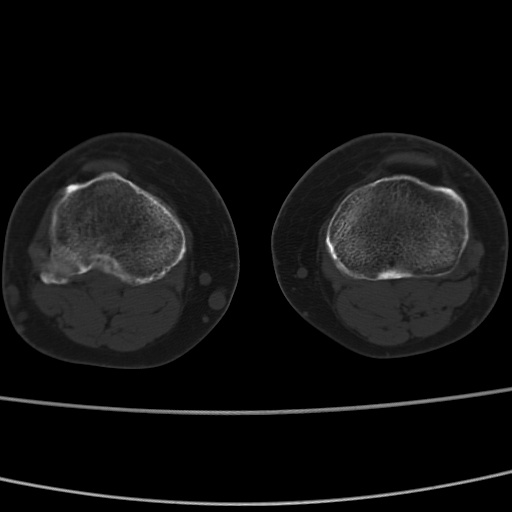

女性,50岁。【请提供患者临床症状体征】

右膝关节退行性改变,关节游离鼠。

右膝关节退行性改变,滑膜黏液囊钙/骨化并游离。

右膝关节退行性改变